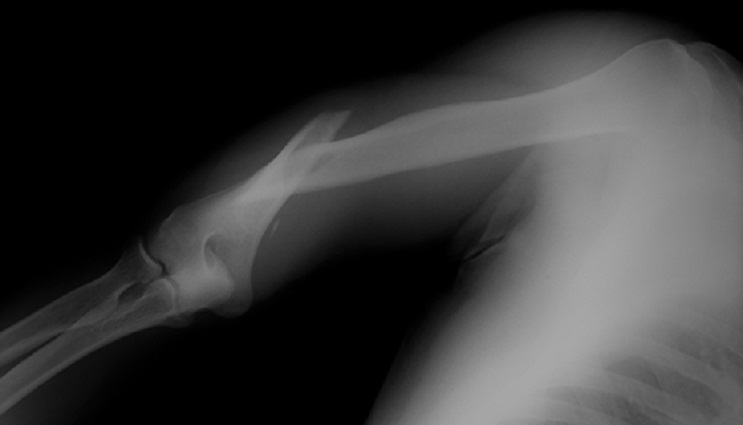

Gambar 2. Ilustrasi Pengapuran Sendi (Osteoartritis)

Sumber: www.healthdirect.gov.au (osteoarthritis)

Proses pengapuran terjadi apabila kartilago atau tulang rawan sendi mengalami kerusakan dan tidak dapat diperbaiki oleh tubuh secara alami.

Pengapuran yang dimaksud adalah terpaparnya tulang di bawah rawan sendi (tulang subkondral) dan kontak antar-tulang inilah yang mencetuskan terbentuknya osteofit atau tonjolan tulang yang mencoba menjadi peredam kejut sebagai pengganti tulang rawan. Tetapi hal ini tidaklah efektif dan pada akhirnya akan menimbulkan proses sklerosis (pengerasan) dari tulang-tulang yang kontak dan mengganggu fungsi sendi (berkurangnya lingkup gerak sendi, nyeri dan kesulitan berjalan).